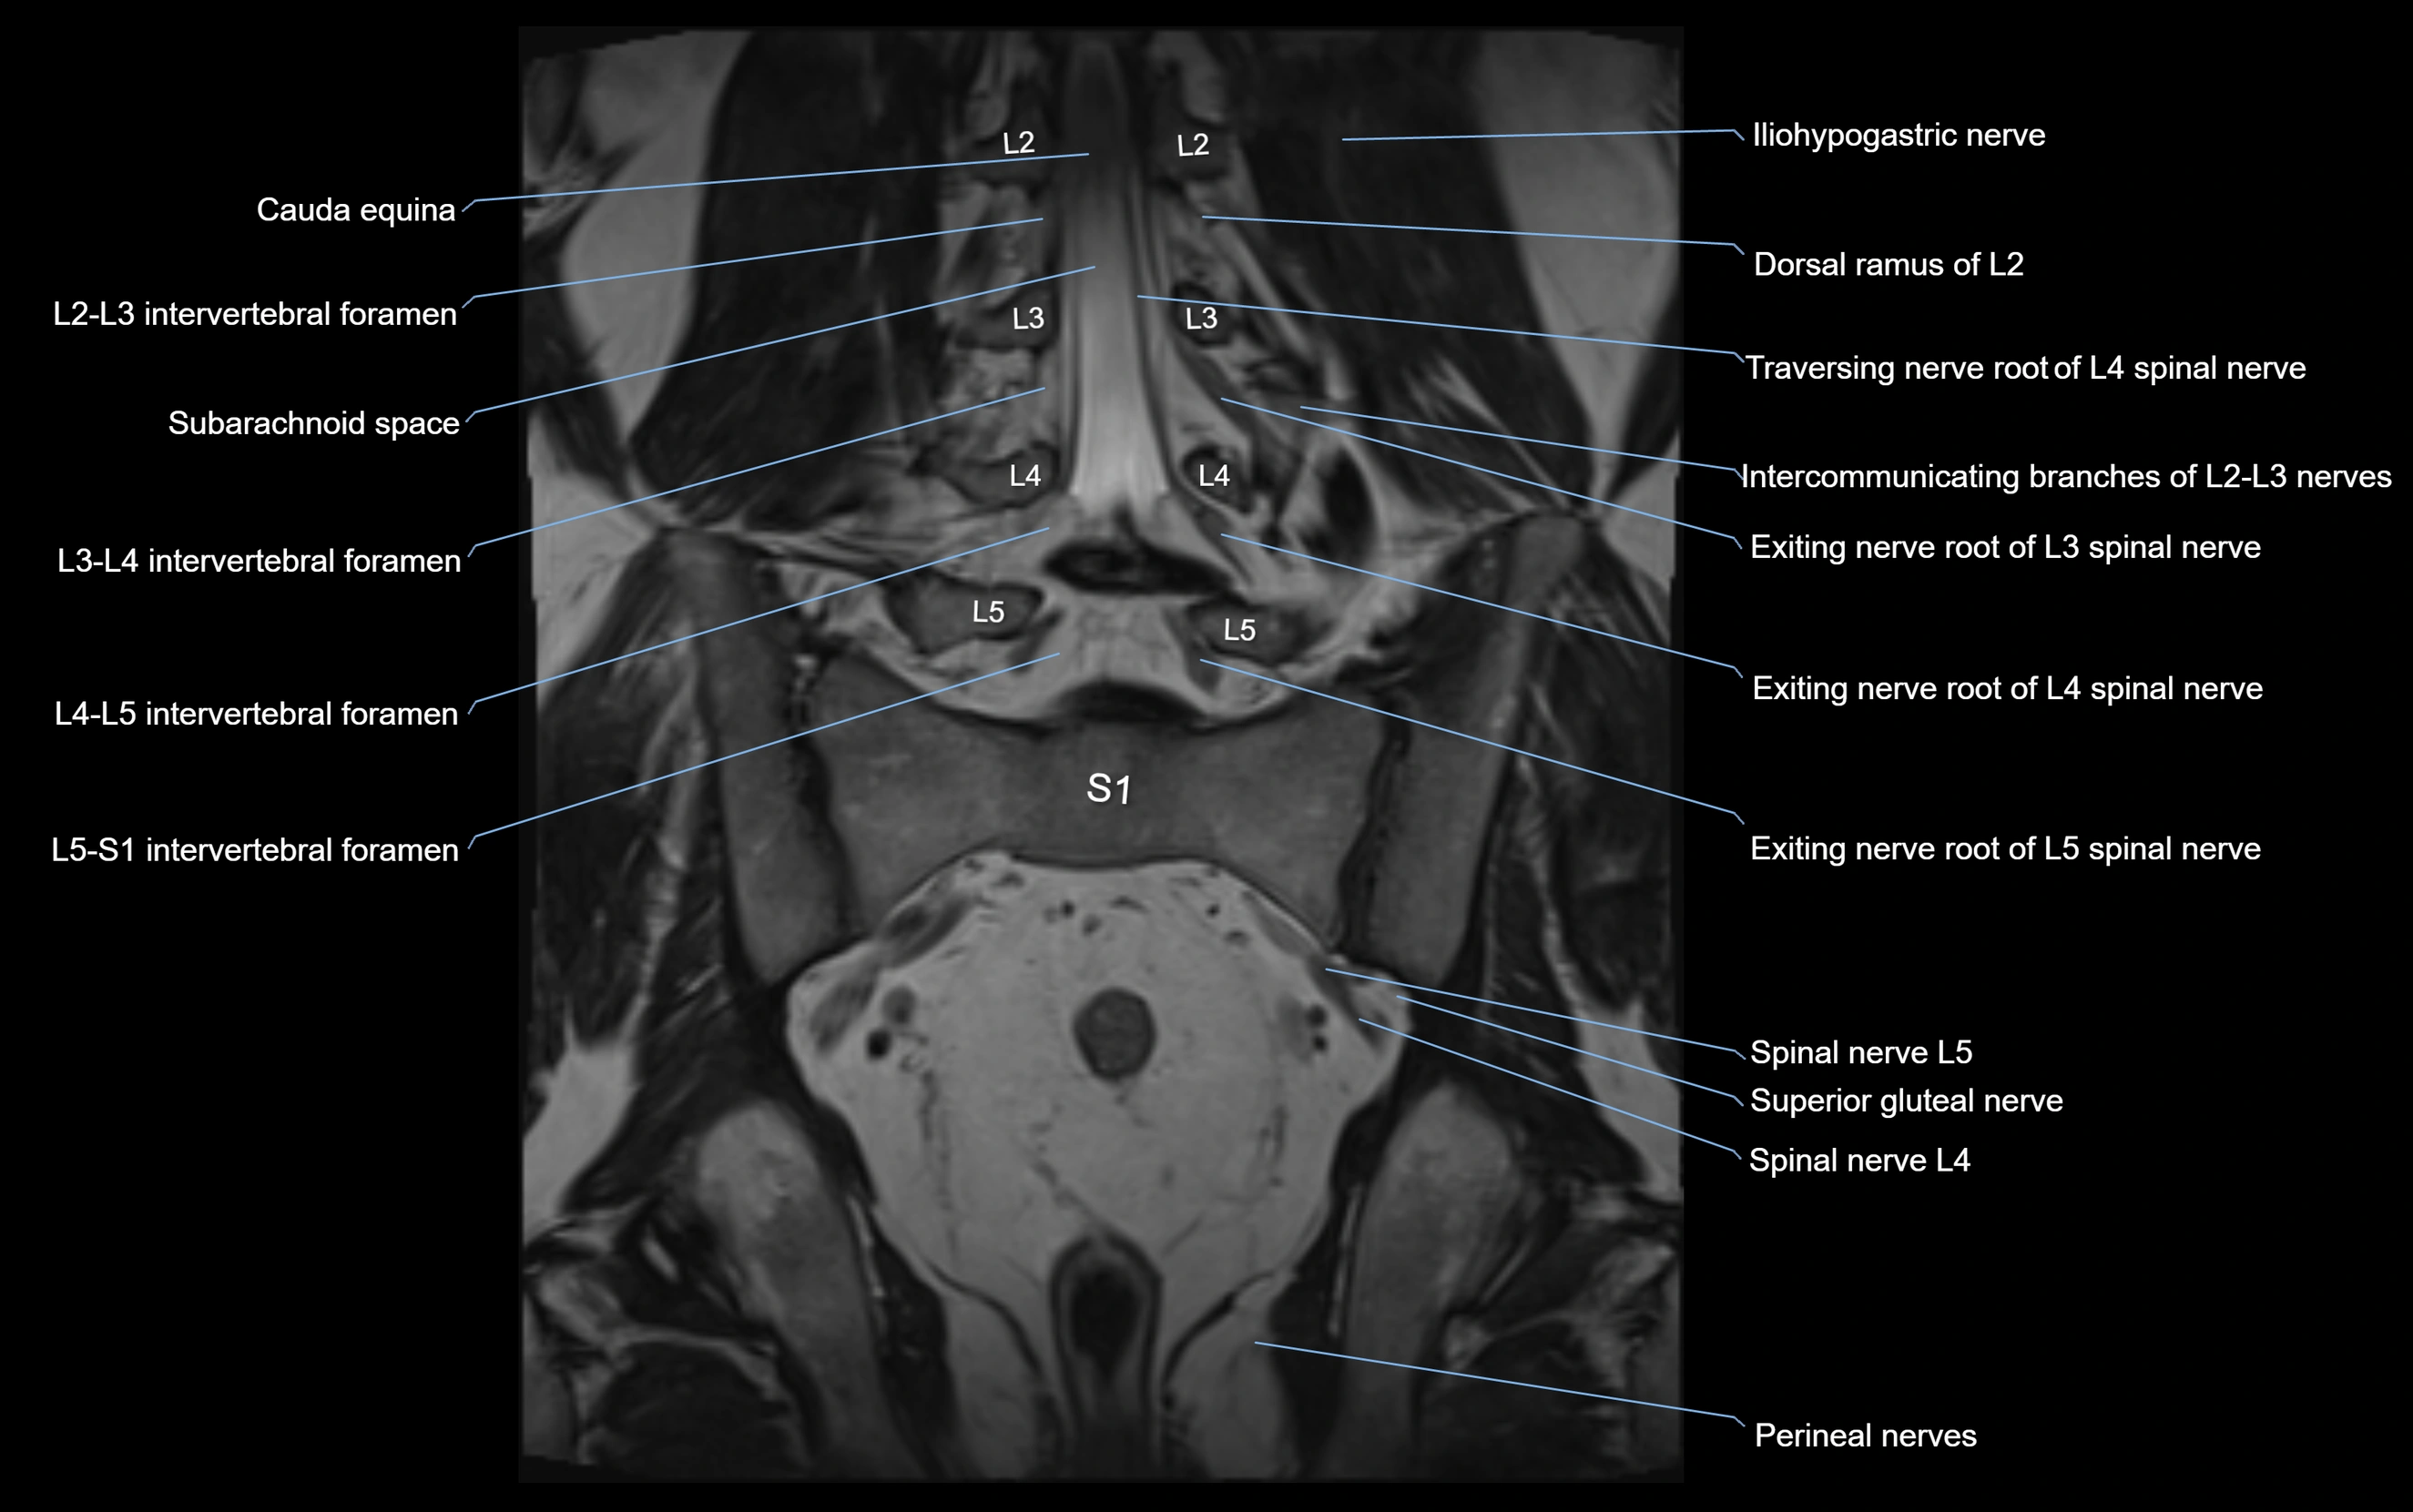

MRI image

image